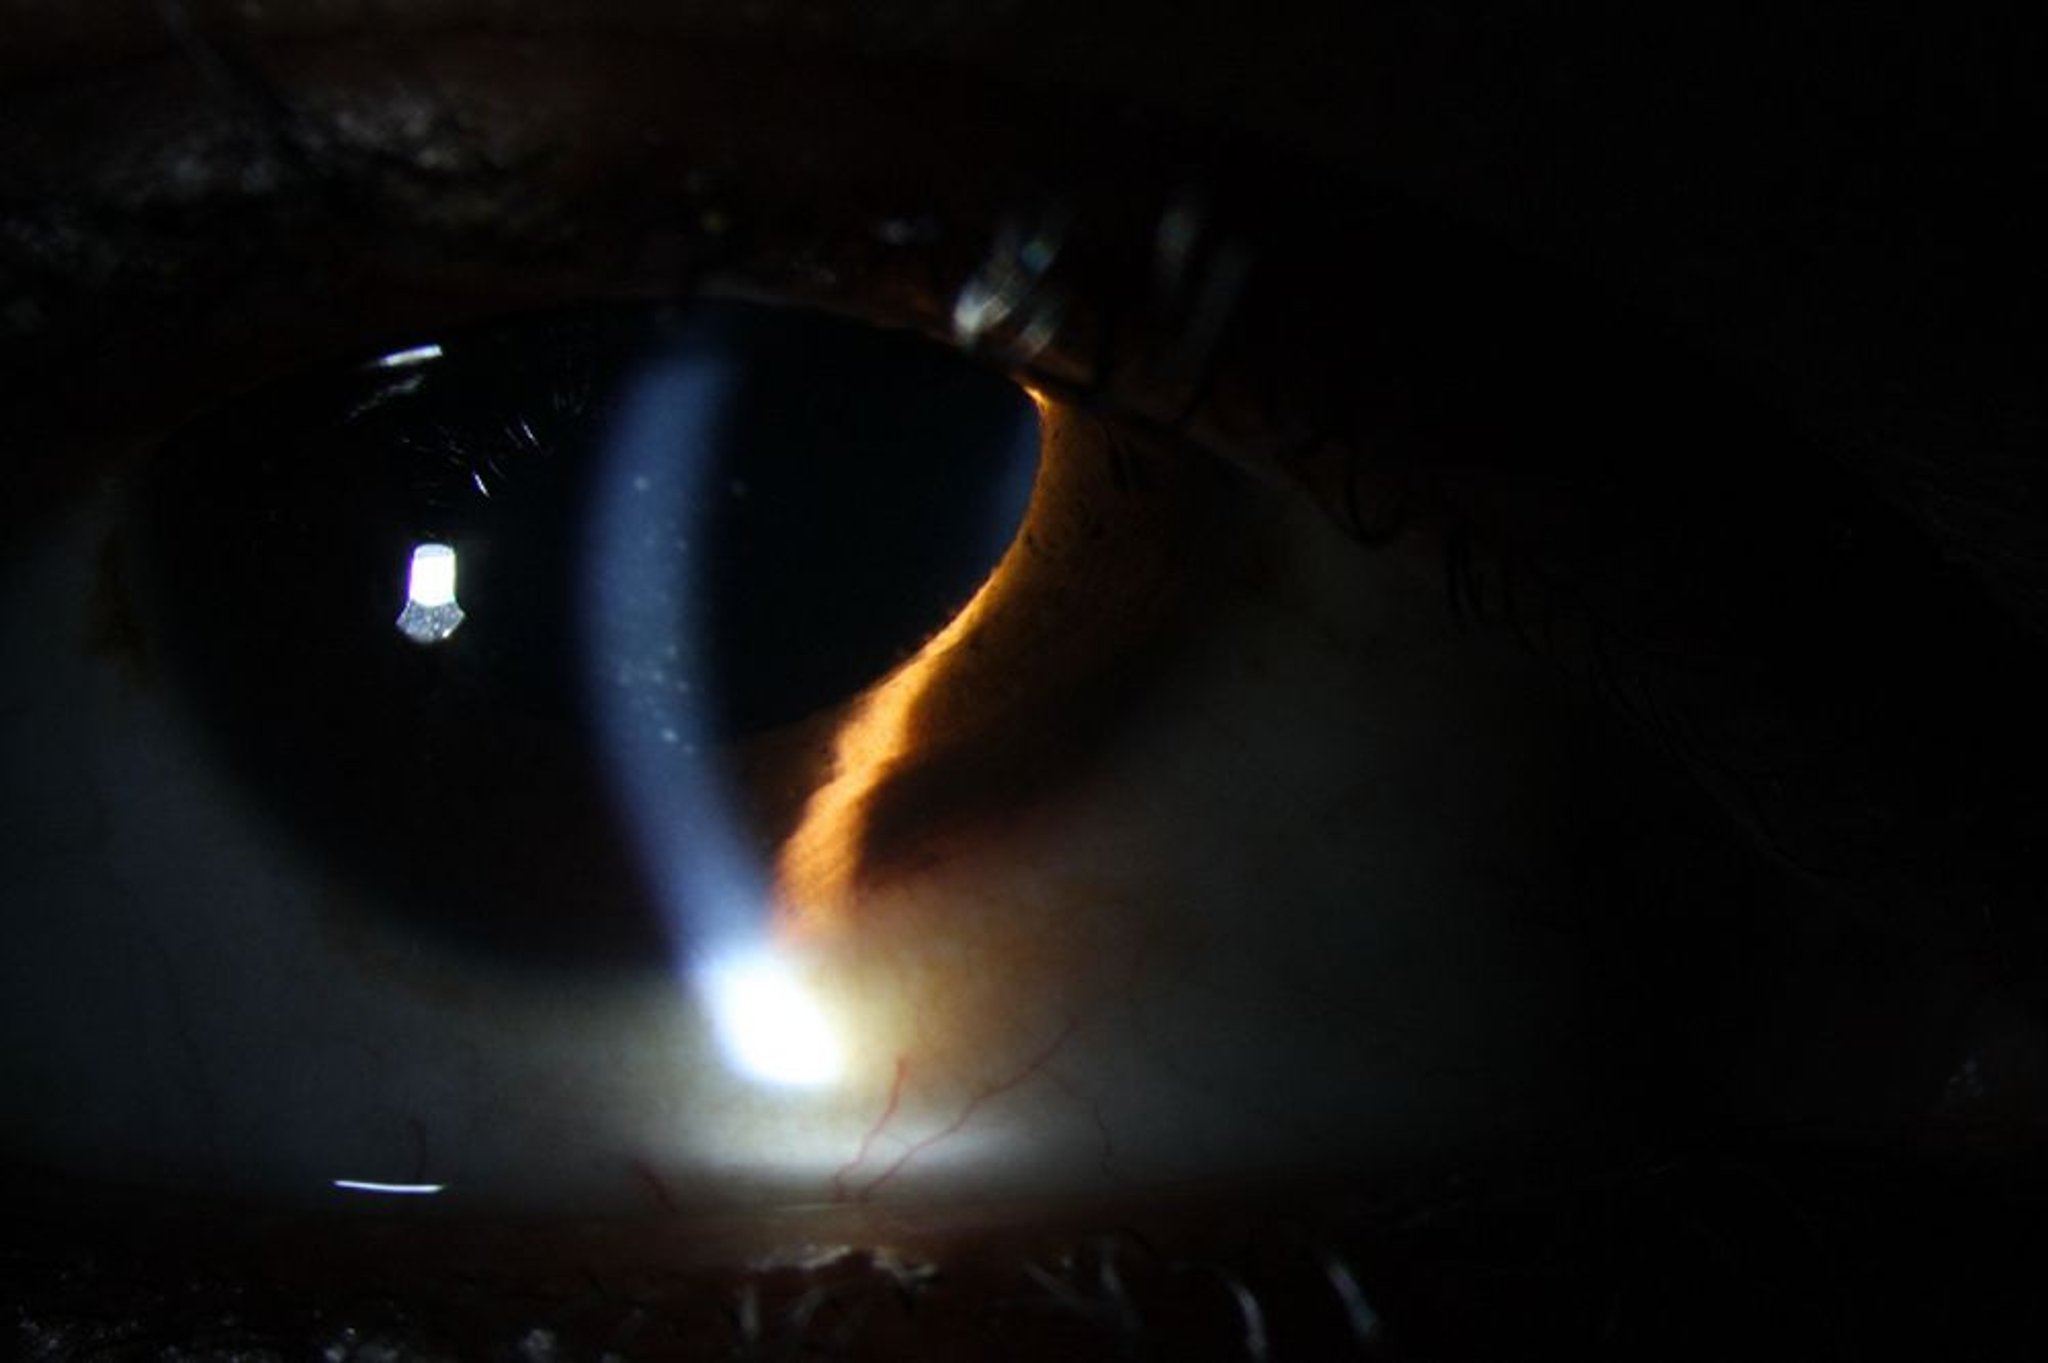

Uveítis (anterior)

La uveítis anterior puede causar eritema, la precipitación de queratina en el endotelio corneano (imagen), así como la presencia de glóbulos blancos y formaciones brillantes (proteínas) en la cámara anterior.

Image courtesy of Sunir Garg, MD.